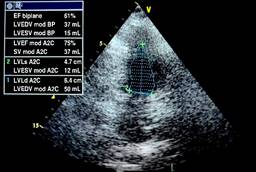

The initial LVEF was 36%, and 48 hours later, it was 47% (Figure 1). The echocardiogram showed important dilation of the left ventricle (Figure 2). The echocardiographic controls performed on the tenth day, at seven and 12 months, showed recovery and normal LVEF, demonstrating complete reversibility at 10 days that continues up to one year (Figure 3). There was no compromise in cardiac output according to measurements in the five echocardiograms performed. The cardiac index was calculated using the Dubois cardiac index estimation formula; the cardiac index was not altered during the development of the pathology.22 GLS is also used to assess left ventricular systolic function in patients with septic shock. It detects subtle changes in myocardial contractility and is more sensitive and accurate in evaluating systolic ventricular function compared to LVEF. We obtained a GLS of -14% initially (Figure 4); in the 12th month of echocardiographic control, normalization of the values was found with a GLS of -20.6% (Figure 5), therefore recovery of systolic function, which is considered normal at values of -18% to -20%. Measurement of variables through direct methods was not possible.

Figure 3: A two-chamber view showing the reversibility of the changes in the morphology of the left ventricle and the recovery of the ejection fraction in the echocardiogram performed one year later. EF = ejection fraction (biplane). A2C = apical two-chamber (view). SV = stroke volume. LVEDV BP = left ventricular end-diastole volume (biplane). LVESV BP = left ventricular end-systole volume (biplane). LVEF = left ventricular ejection fraction. LVEDV = left ventricular end-diastole volume. LVESV = left ventricular end-systole volume. LVLs = left ventricular length at end-systole. LVLd = left ventricular length at end-diastole.